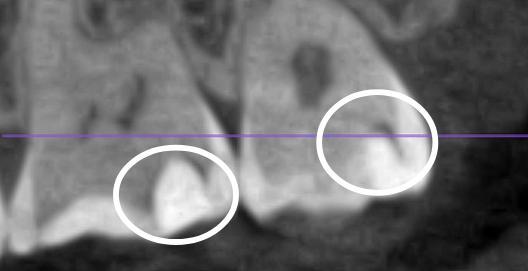

Недавно обращалась к терапевту с целью проверки состояния полости рта. На что получила ответ, что ряд жевательных зубов вызывают вопросы, одному даже нужна реставрация. До этого в течении полугода посещала 3ех терапевтов, приносила КТ, ответ один - никакого кариеса нет. По ощущениям пломба на одном из зубов имеет неровные границы, реагирует болью на сладкое. В этот раз сделала КТ с расшифровкой от известной сети независимых клиник. Отчета по зубам пока не получила, но КТ выдали сразу. Меня смущает несколько зубов. Может ли это быть кариес? 1(сверху) - 6 и 7 справа, 2/3 - 6ка слева, вид сбоку, вид спереди

Это скорее всего лечебные прокладки из не контрастных материалов...

Согласна с коллегой